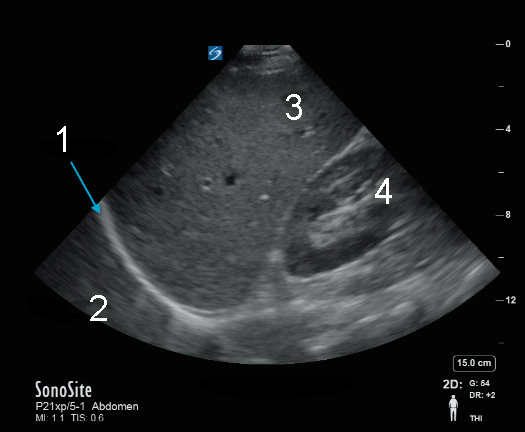

eFAST/RUSH 右上腹 (RUQ) 肝脏/右肾图像

膈膜

胸膜腔

肝脏

肾脏